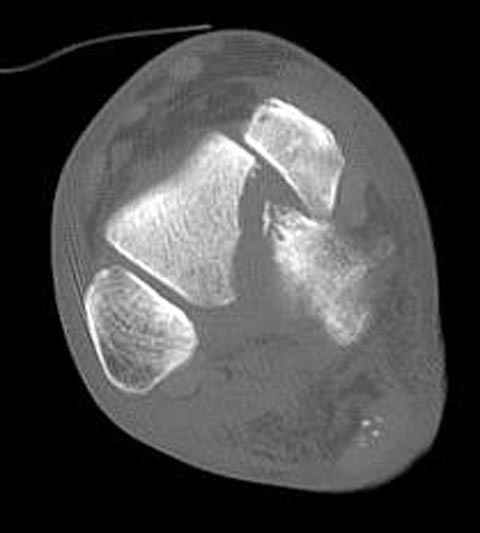

Вдогонку по поводу перелома таранной кости, больная 81, не страдает диабетом, перелом закрытый, в первый же день поступления ограничились временным наружным фиксатором (как на снимке).

За пару недель насчитал 5 больных с переломом таранной кости, из них двое с двусторонним повреждением.

Из-за отека на стопе тактика лечения у всех была

одинаковая: временная наружная фиксация до спадения отека, при изолированных переломах они выписывались домой и через дней 7 госпитализировались на оперативное лечение.

Примеры на снимке...